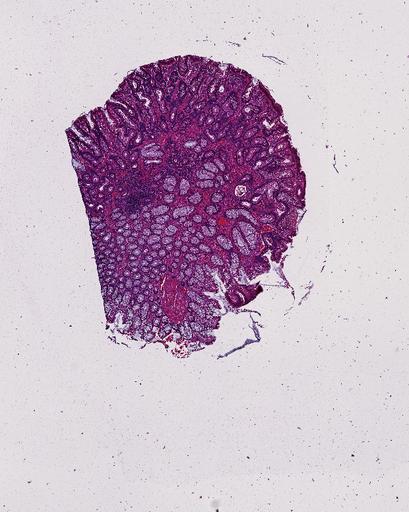

High‑resolution three‑dimensional (3D) tissue atlases promise to redefine how we study cellular architecture‑function relationships in human tissues. Large-scale consortia such as the Human Bimolecular Atlas Program (HuBMAP) systematically build detailed 3D organ maps by profiling serial tissue sections with single-cell spatial technologies. However, an accurate and efficient reconstruction method that can handle atlas-scale datasets remains elusive. We introduce Space-map, an open-source method that integrates single‑cell coordinates with optional histological image features to assemble serial sections into 3D models. Space‑map combines multi‑scale feature matching with large‑deformation diffeomorphic metric mapping, delivering global reconstructions while preserving local micro‑anatomy. To demonstrate the capability of Space-map, we generated a serially sectioned spatial transcriptomics (Xenium, ~2.9M cells) dataset and a spatial proteomics dataset (CODEX, ~2.4M cells). Applying Space-map to these single-cell spatial maps, we built three 3D models for both diseased (colon polyp) and reference colon tissues. These high-resolution 3D models showcase the intricate structure of the human colon across different states. Space-map is fast and highly efficient. We demonstrated its performance and accuracy using in‑house and public datasets. The result shows that Space‑map is 10 times faster and ~2‑fold more accurate than PASTE and STalign, making 3D atlas reconstruction more accessible. Our study provides a new robust and user-friendly software available at https://github.com/a12910/spacemap that can be easily applied for constructing molecular 3D tissue maps of human organs at single-cell resolution.